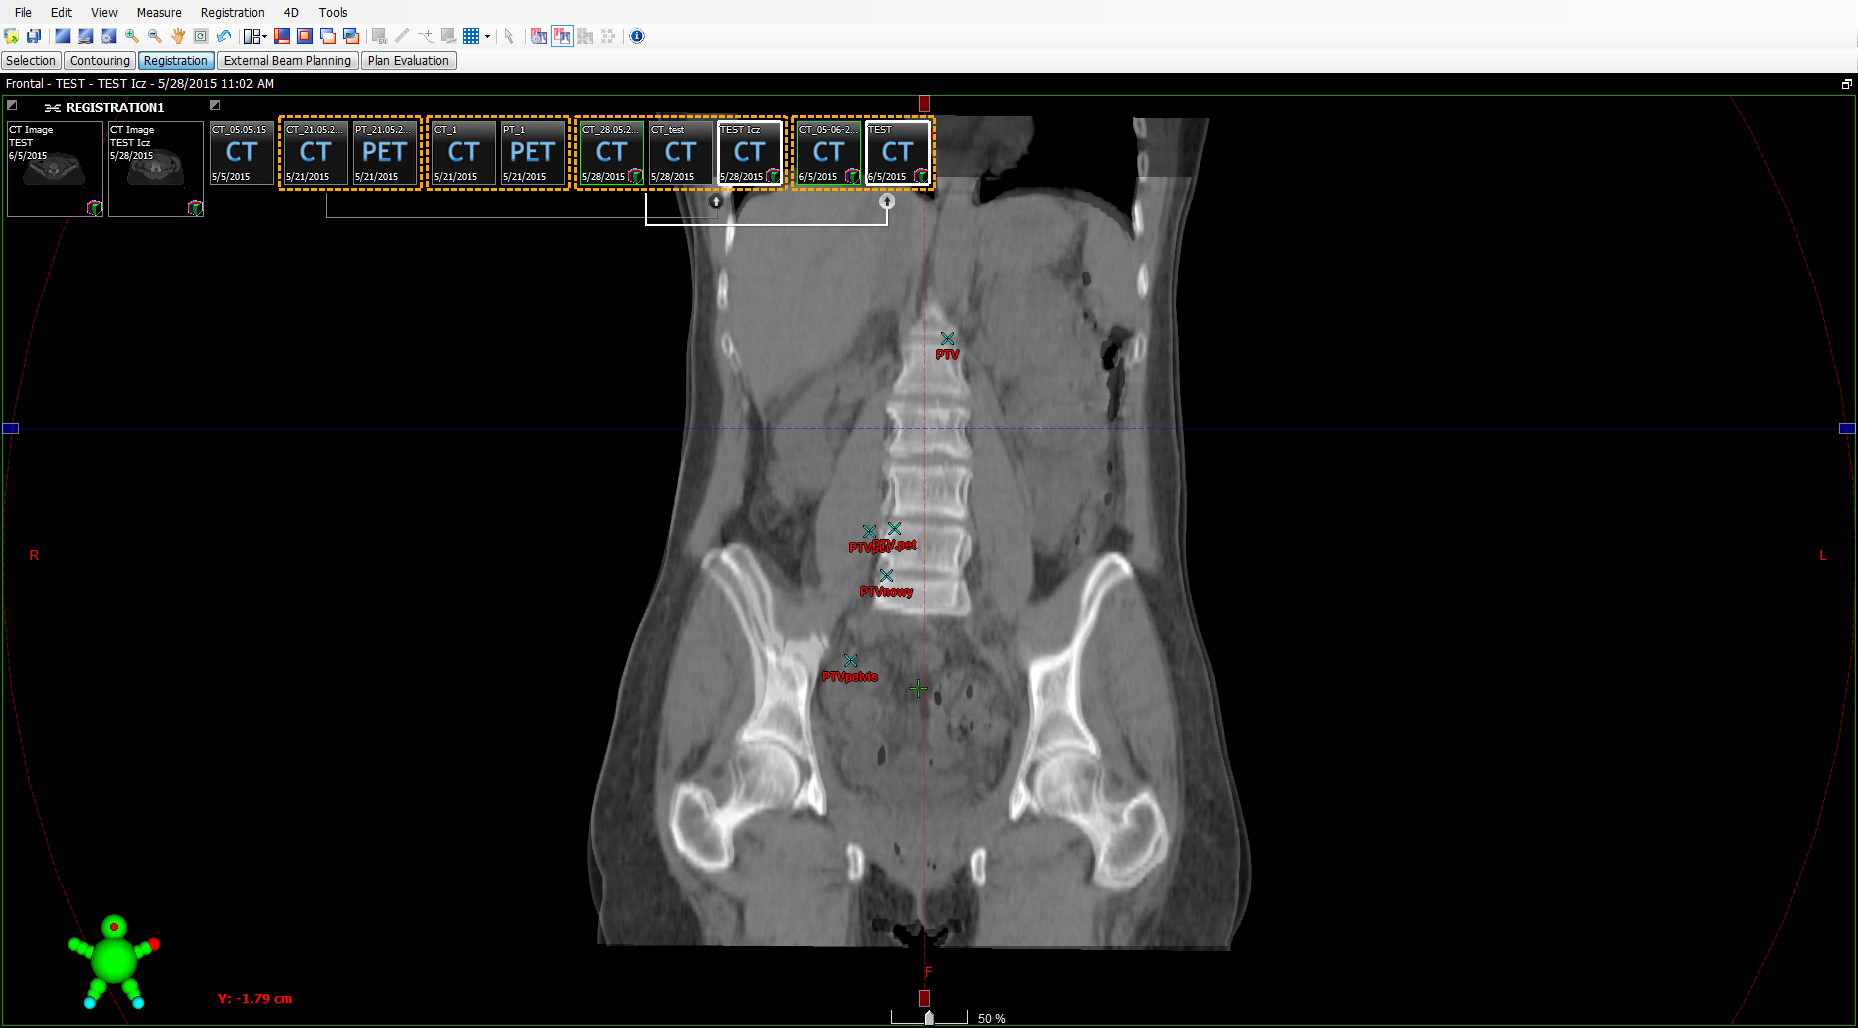

Radioterapia w leczeniu raka szyjki macicy odgrywa bardzo dużą rolę. Jej zastosowanie oraz objęcie obszarem tarczowym napromienianych struktur zależy od zaawansowania choroby nowotworowej. Zastosowanie nowoczesnych technik planowania oraz weryfikacji ułożenia pacjenta pozwala na ograniczenie marginesu tkanek zdrowych i toksyczności całego leczenia radioterapeutycznego. Trzeba jednak brać pod uwagę wystąpienie czynników wpływających na dokładności przeprowadzonego leczenia. Takim czynnikiem jest też rotacja miednicy u kobiet. Występuje ona w sposób mimowolny, jak również trudny do wychwycenia na etapie planowania. Nierzadko powiązana ze stresem czy komfortem pozycji, w jakiej napromieniany jest pacjent. Tylko właściwa interpretacja oraz wczesne wychwycenie powyższej może wpłynąć na działania przygotowawcze. W artykule zaprezentowano różnice występujące zarówno w obszarach tarczowych, jak również narządach krytycznych w przypadku zrotowania kości miednicy.